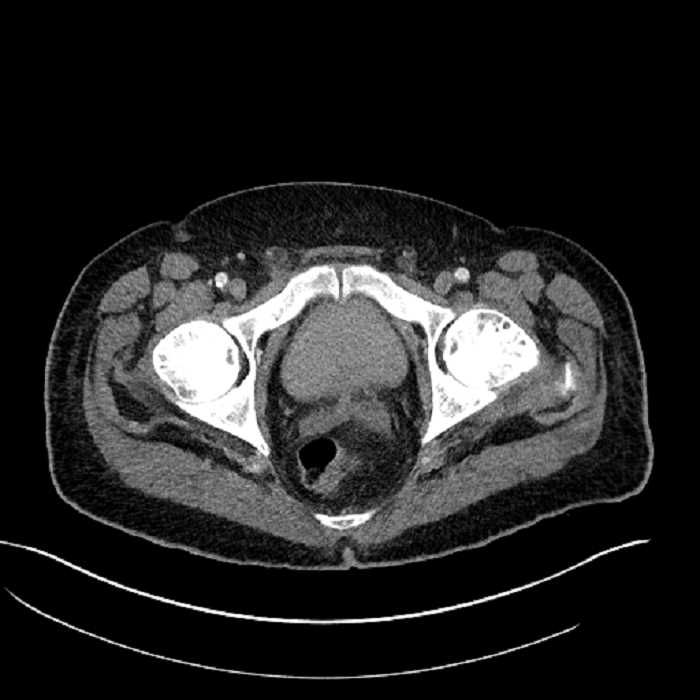

• High grade stenosis of the left common iliac artery, with the left internal and external iliac arteries remaining patent

High grade stenosis of the left common iliac artery. The left external and internal iliac arteries are patent.

Hepatic abscess showing the double target sign with low density internally surrounded by a thin inner enhancing rim (red arrow) and ill-defined outer low density rim (yellow arrow). Blue arrow indicates an internal septation. Red arrows: additional smaller subcapsular abscesses. Red arrow: focal contained perforation associated with diverticulitis.